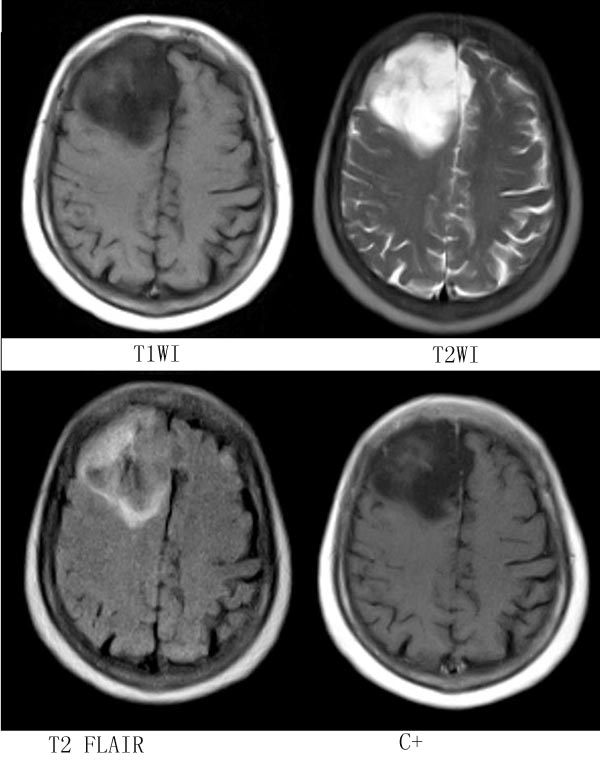

女,64岁,ct示右侧额叶占位,平扫无钙化,增强无强化,mr平扫+增强,请大家诊断.

右侧额叶占位性病变,病灶累及脑灰白质,信号较均匀,增强扫描病灶强化不明显,边界较清楚,相对于病灶本身大小来说,占位效应较轻,考虑为分化较好的胶质瘤,以胚胎发育不良性神经上皮榴或混合性胶质瘤可能性大(dnt).

病灶位于右额叶,呈不均匀长t1长t2信号,部分液化,占位效应不明显,无强化,临近颅板无受侵,考虑分化程度较高的胶质瘤。

右额叶占位性病变,信号不均,边缘不清,增强轻度不均匀强化,考虑星形细胞瘤(3-4级)

原因:年龄符合;部位符合;影像flair有条状低信号考虑为钙化;增强不强化。

考虑星形细胞瘤 诊断依据:TIW低信号 T2W高信号 瘤体靠近皮层下,周围是个囊腔(“囊在瘤内”),瘤体强化不明显,部分跨越中线,浸润及占位效应不明显,愈后较好。